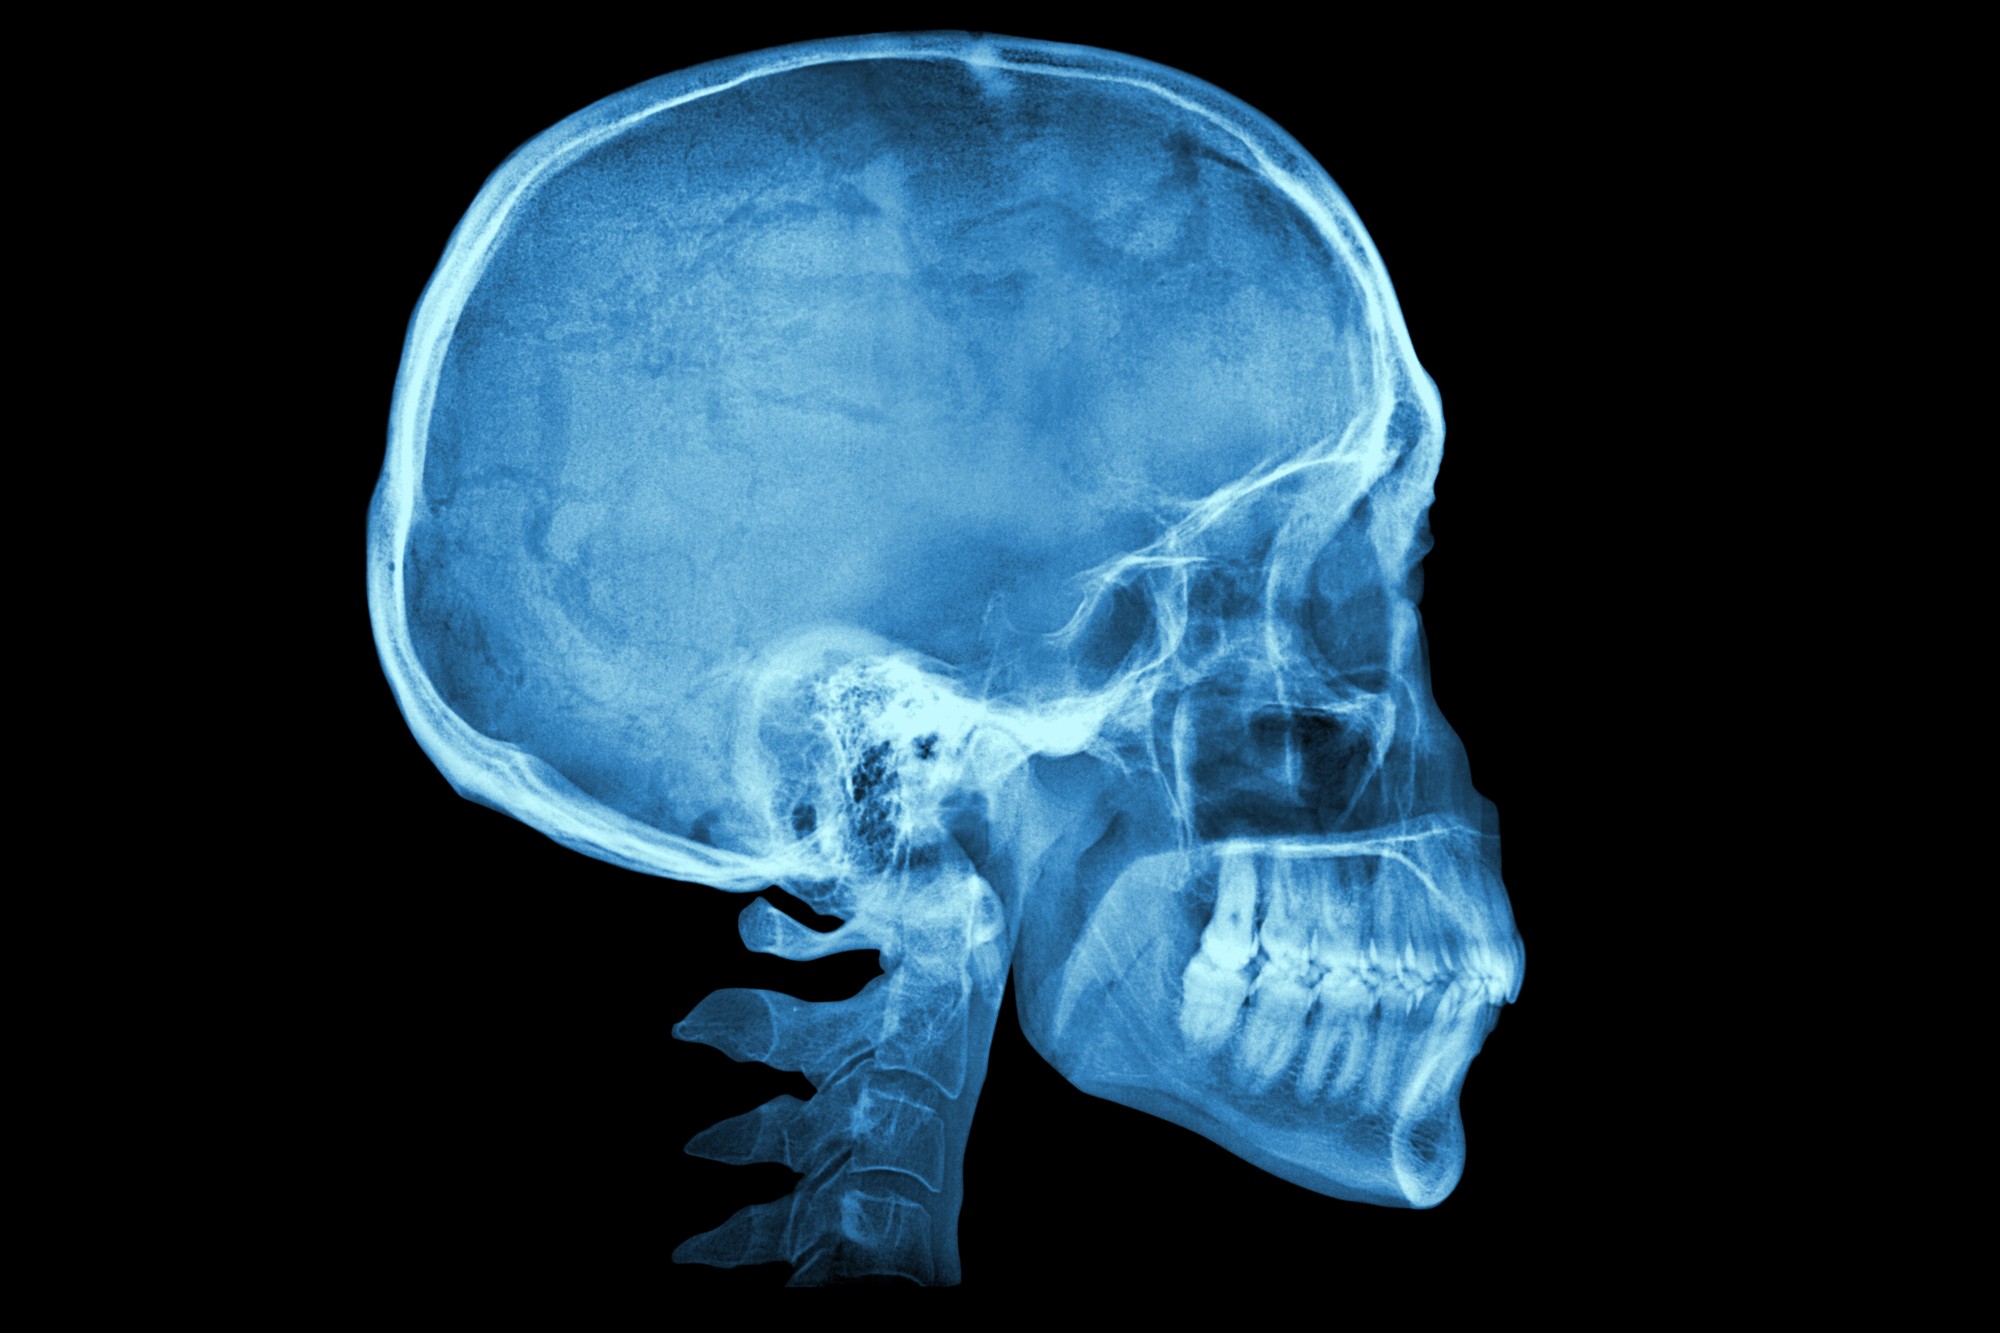

"Me salió la muela del juicio y estaba negra, y yo estaba como 'Dios mío, mis dientes se están pudriendo", dijo el joven en el clip de TikTok. "Y resulta que mi mandíbula está negra, y probablemente el resto de mi cráneo y la mayoría de mis huesos [lo están también] según mi médico".

Es un trastorno denominado alcaptonuria que conduce a ocronosis. La deficiencia enzimática que produce, provoca la acumulación de ácido homogentísico (HGA) a una velocidad 2000 veces superior a la normal. El HGA se une al cartílago, al hueso y a los pigmentos, volviéndolos negros, de ahí el nombre popular de enfermedad del hueso negro.

Y una vez que comienza el proceso de decoloración es rápido y permanente, pero la enfermedad de los huesos negros (cuando es causada por minociclina) es bastante benigna y no se asocia con necrosis o muerte del tejido.